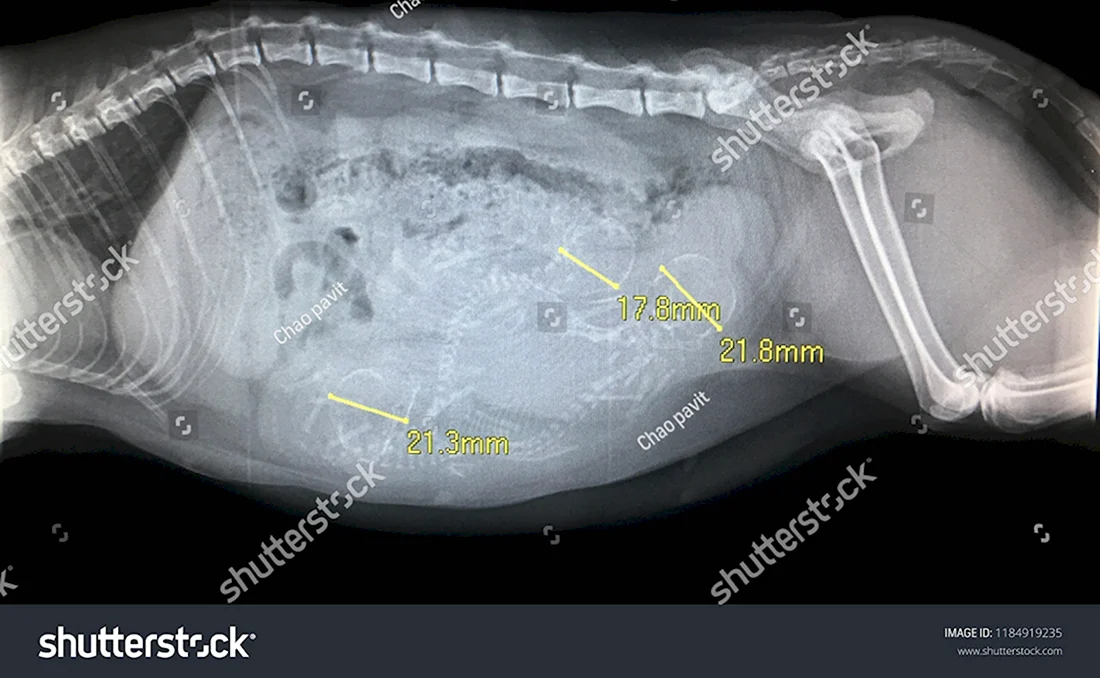

В данной статье представлена уникальная галерея фотографий, которые запечатлевают нежное чудо жизни — котят в утробе кошки. Вас ждут 35 потрясающих фото и картинок, позволяющих заглянуть в мир развивающихся маленьких созданий. Приглашаем вас окунуться в эту удивительную галерею и насладиться прекрасными видами эмбрионов кошачьих детенышей.

Так трогательно и волнующе наблюдать за процессом формирования новой жизни внутри мамы-кошки на этих удивительных фотографиях.